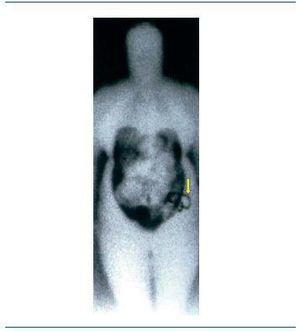

Figura 1. Gammagrafía anterior corporal a los 40 minutos con solución coloide marcada con Tecnecio99 intraperitoneal tras administración directa a través de catéter peritoneal.